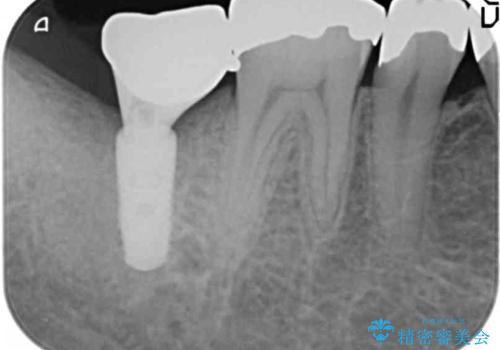

患者様のご希望によりPGA(金白金合金)クラウンによる補綴を行いました。

「金歯は咬み心地もいいし、見た目もカッコイイ!」と喜んで下さいました。

自然な使用感にご満足頂き、他の部位もPGAクラウンによる治療をご希望され現在治療中です。

インプラントの種類:アルファタイト

クラウンの種類:PGA(Platinum Gold cast Alloy・金白金合金)クラウン